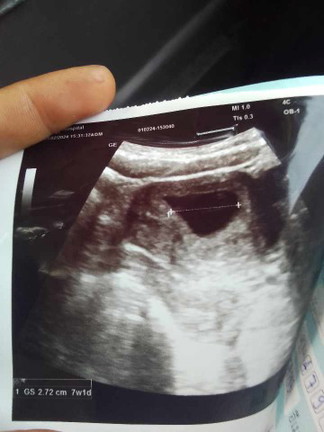

ไปฝากครรภ์รอบเเรกหมอว่า น้องพึ่ง7W เเต่อัลตราซาวด์ไม่เจอตัวน้อง เเม่ๆท่านอื่นเจอน้องกี่วิคคะ